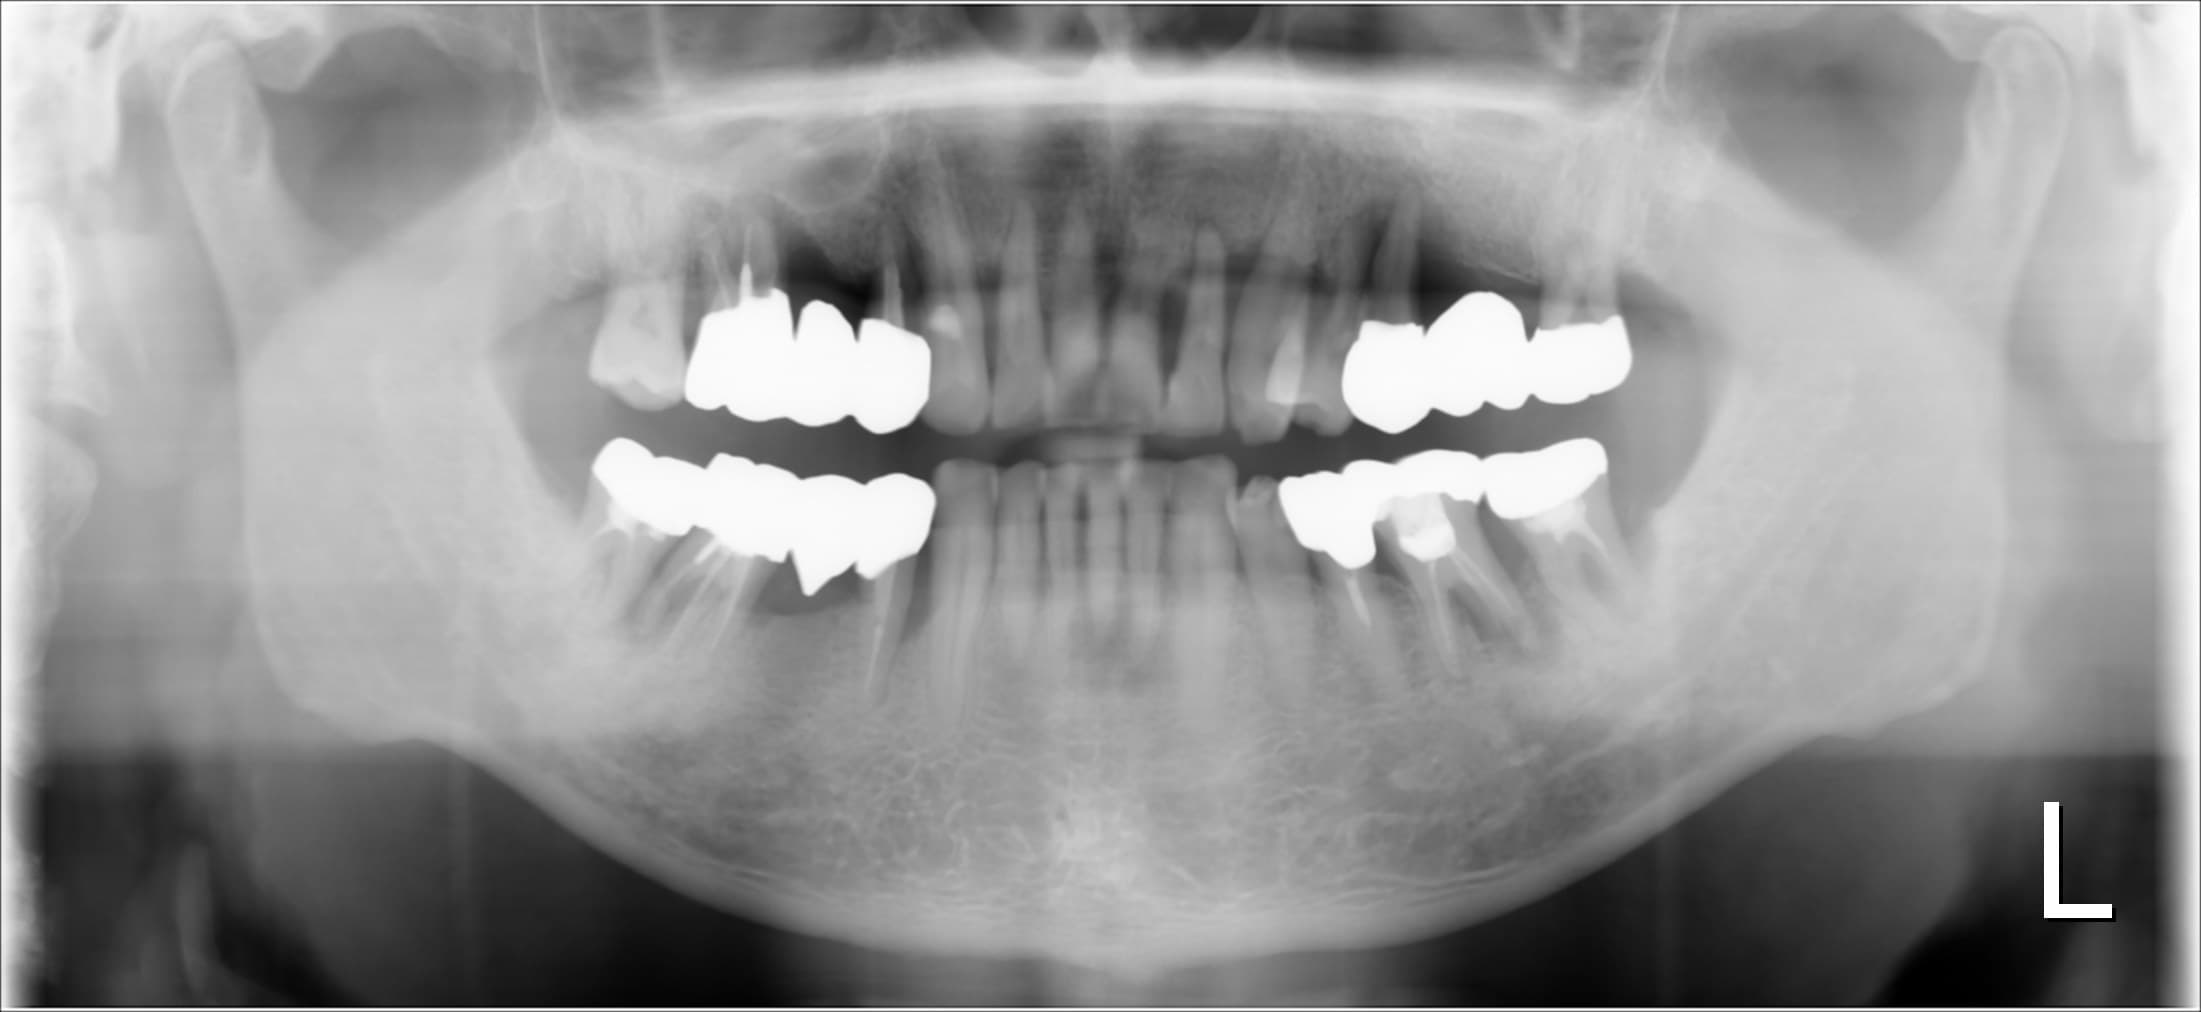

レントゲン写真